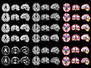

Image identification by machine learning models is a major application of artificial intelligence (AI). And, with ever-improving capabilities, the use of these models for medical diagnostics and research is becoming more commonplace. Doctors analysing X-rays and mammograms, for instance, are already being assisted by AI technology, and models trained to identify signs of disease in tissue sections are also being developed to help histopathologists. The models are trained with microscope images annotated by humans – the image, for example, shows a section of rat testis with signs of tubule atrophy (pale blue shapes) with other coloured shapes indicating normal tubules and structures. Once trained, the models are tasked with categorising unannotated datasets. The latest iteration of this technology was able to identify disease in testis, ovary, prostate and kidney samples with exceptional speed and high accuracy – in some cases finding signs of disease that even trained human pathologists had missed.